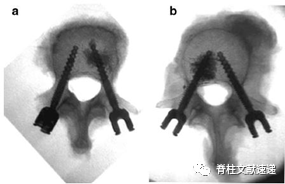

图注:显示椎体骨水泥增强后一侧用1ml (a)或3ml (b)

结果显示:椎体骨水泥强化明显增加了螺钉的抗拔出力,1ml骨水泥增加了41%,3ml骨水泥相比增加了51%,两者间无显著统计学差异。

结论认为骨水泥增强术可显著提高椎弓根螺钉的稳定性。将骨水泥用量从3ml减少到1ml并没有显著影响椎弓根螺钉增强效果。考虑到在增强过程中水泥渗漏的高风险,建议每个椎弓根螺钉使用1ml的骨水泥强化。